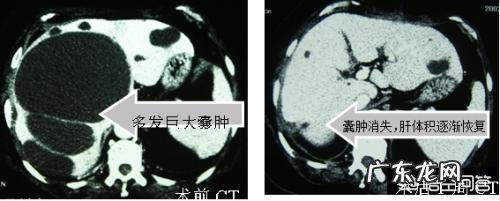

肝囊肿一般是良性的只要直径不超过3公分一般不需要治疗 , 但是直径超过3-5公分以上或者是肝脏引起的肝区疼痛时 , 就需要进行一定的治疗了 。

早期的肝囊肿 , 注意饮食有节 , 营养均衡 , 多数不需要进行特定的治疗 。但若肝囊肿发展到一定程度 , 应配合主治医生进行正规的治疗 。